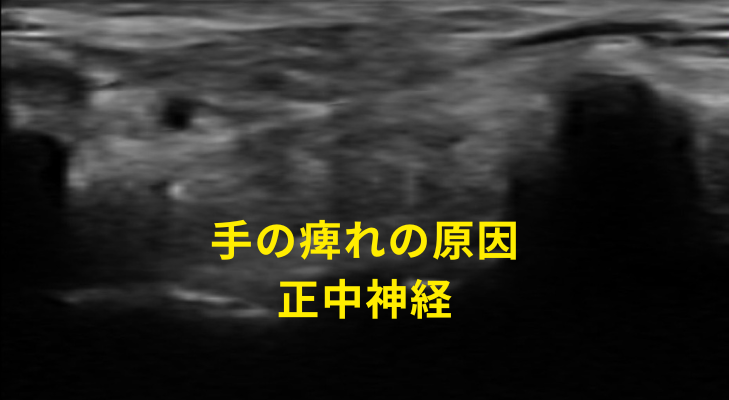

手根管症候群の

原因と症状を

エコーで見極める

その症状を対処するには

正中神経

エコー検査による原因の追究

当院では刈谷市で珍しいエコーを用いて、手根管症候群の原因となる神経や筋膜によるコリをしっかりと見極めます。